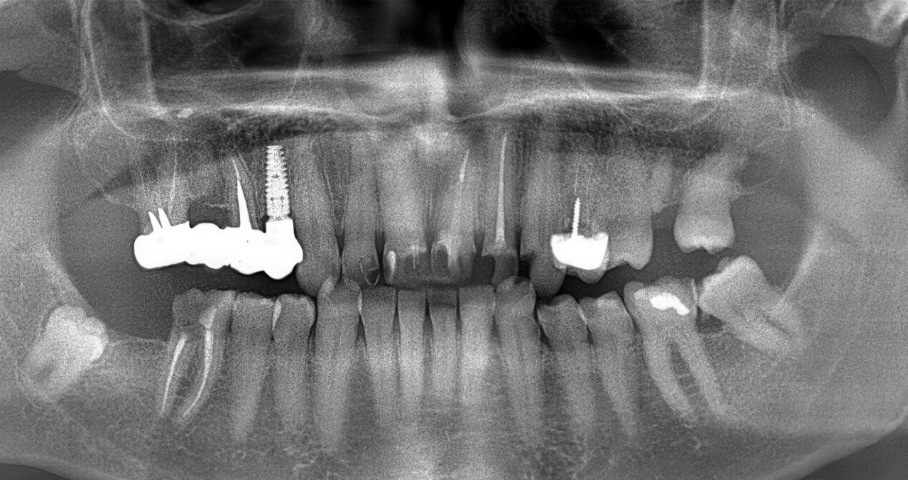

Cuando un implante dental se pierde, muchas personas piensan automáticamente que “no se integró”. Sin embargo, esa es solo una de las posibles causas y suele ocurrir en las primeras semanas tras la colocación. Lo que genera más dudas es cuando un implante que llevaba años funcionando correctamente empieza a dar problemas. Aunque no es lo habitual, sí es posible que un implante fracase a largo plazo. Y cuando ocurre, casi siempre hay factores concretos detrás.

El fracaso temprano se produce cuando el implante no llega a unirse correctamente al hueso. En cambio, el fracaso tardío aparece meses o incluso años después, cuando el implante ya estaba integrado y en uso. Entender las causas reales permite prevenir y, en muchos casos, actuar antes de que el problema sea irreversible.

La periimplantitis es una inflamación de los tejidos que rodean el implante y que provoca pérdida progresiva de hueso. Suele estar relacionada con la acumulación de placa bacteriana y una higiene insuficiente.

Con el envejecimiento o por determinadas patologías (como periodontitis previa), puede producirse una reabsorción ósea progresiva alrededor del implante. Si el soporte disminuye en exceso, el implante puede perder estabilidad.